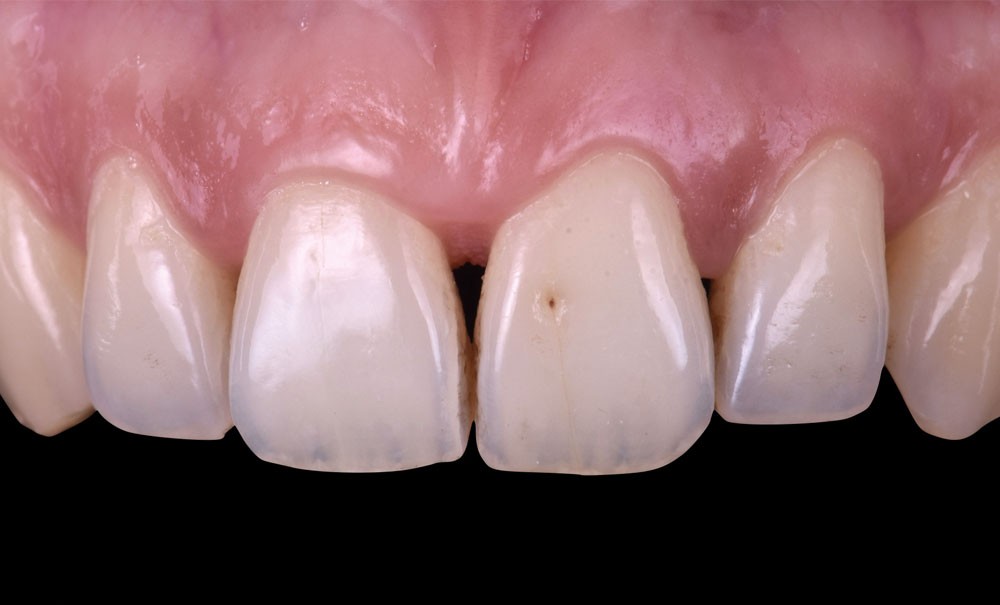

Si les techniques de reconstruction papillaire présentent des résultats non prédictibles, les facettes céramiques peuvent être une réponse fiable au problème des triangles noirs mais imposent une préparation plus marquée. En effet, pour obtenir un profil d’émergence adéquat et une bonne fermeture de l’espace interproximal, il faut préparer les surfaces de contact et venir chercher la ligne de transition palatine, obligeant à retirer une quantité de tissu sain non négligeable.

La fermeture des triangles noirs en technique directe avec des résines composites offre une alternative très favorable avec une approche non invasive, esthétique, un coût réduit et une possibilité de réintervention aisée. Plusieurs méthodes ont été proposées : réalisation à main levée sans matrice (à proscrire), avec bande de matrice transparente plate ou galbée, avec matrice postérieure customisée et utilisée verticalement… Il faut bien comprendre qu’aucun coin en bois ou plastique ne pourra être employé pour stabiliser cette matrice, car il empêcherait la création d’un profil d’émergence anatomique convexe en induisant une déformation concave de la matrice à sa base.